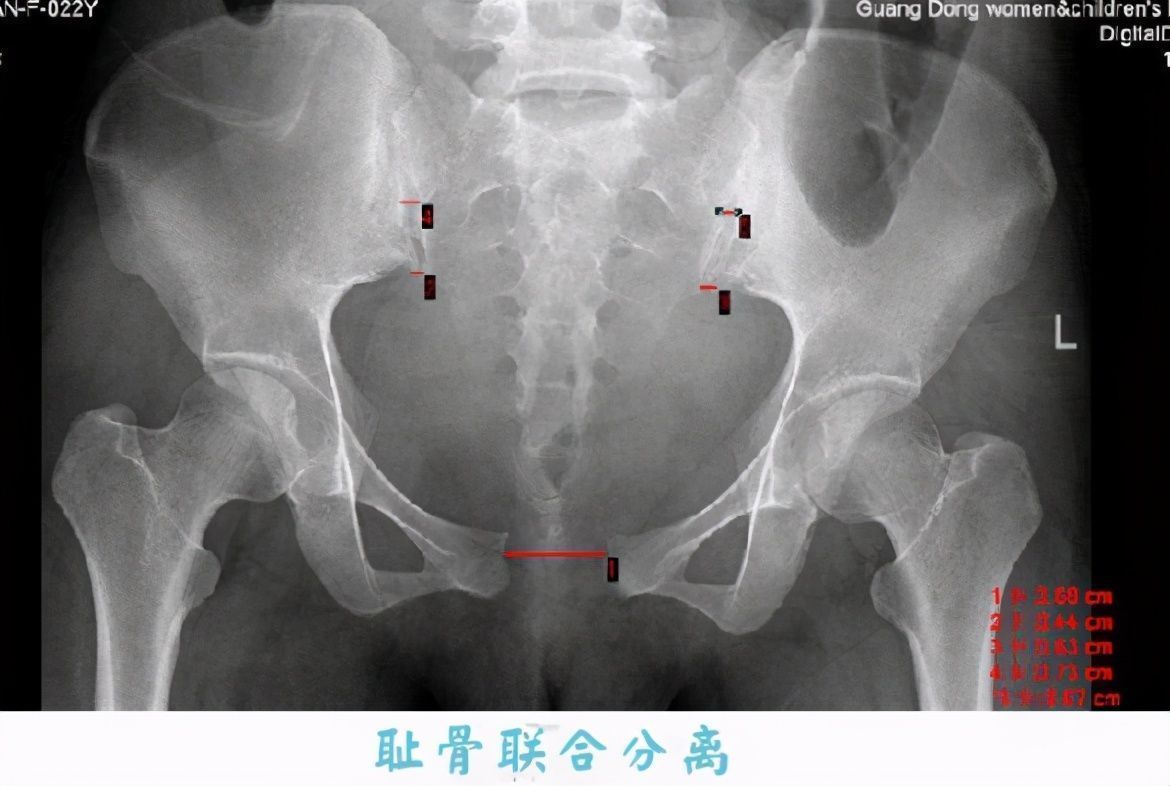

我们先来看一组对比图:

文章插图

从这张图上可以看出,正常的耻骨几乎是连接在一起的,而孕晚期耻骨联合处会出现分离的现象,正如你说看到的,有两块骨头在分离。

一般来说,孕晚期两块耻骨会分离到0.3-0.4厘米,而耻骨分离的时候会刺激到痛觉神经,所以就产生了疼痛。当然耻骨分离也是有原因的,这是为了宝妈能更容易分娩。我当初耻骨痛的时候,婆婆就在一旁说,越痛越好生产。虽然耻骨疼痛的程度跟生产之间没有必然联系,但是耻骨分离的确是为了让孕妈更好分娩。